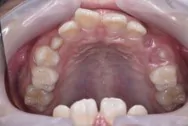

拡大床で対応できる症例

拡大床の症例

症例の概要

患者さんは7歳の女の子で、下の永久歯が2本生えた状態で叢生(ガタガタ)を認めました。

このままでは永久歯が正常に生えない為、拡大床でアーチを広げ前歯4本がしっかり生えるように矯正しました。

拡大床は1日16時間装着していただき、真ん中に見える装置を5日に1回、回してもらい拡大していきました。

治療期間は1年半でしたが、この期間は前歯がしっかり生えそろうまで、確認する必要があります。